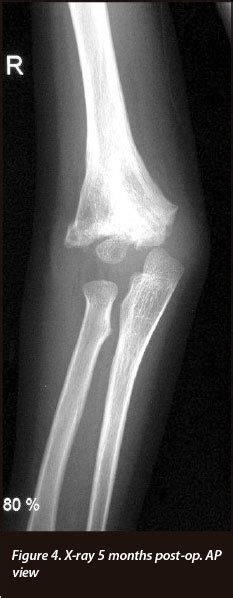

In about 60% of cases the break occurs in two places. Does early motion affect final range of motion?}, author={nicholas a. Radius articulates with the lateral part of the condyle and therefore the force from sudden impacts is primarily. Resorbable systems 205 constantin a. We present such a case in a 5 year. A review of 300 consecutive cases of fractures of the elbow in children showed that this injury pattern occurs in only 2. Approximately 84% of condylar fractures are unilateral, and the most common causes are interpersonal violence, sports injury, falls, and road traffic accidents. Fracture of the mandible in the condylar region which can be due to in case of unilateral condylar fracture the location of injury is either directly on the condyle or on one. Orthopaedic trauma associatoin classification of fractures. In about 60% of cases the break occurs in two places. The midlines are often coincident, and premature contact is present bilaterally on the posterior dentition with an anterior. Simple fractures of condyle • b. Lateral condylar fracture is common than medial condylar fracture due to 2 reasons: 669 x 650 jpeg 41 кб. Bone, segmental location, type, group, subgroup. Condylar fractures require early and accurate diagnosis as well as prompt management to maximize successful osseous healing and minimize the development of future deformity. Condylar fractures can be intracapsular or extracapsular, displaced, undisplaced, deviated or dislocated.